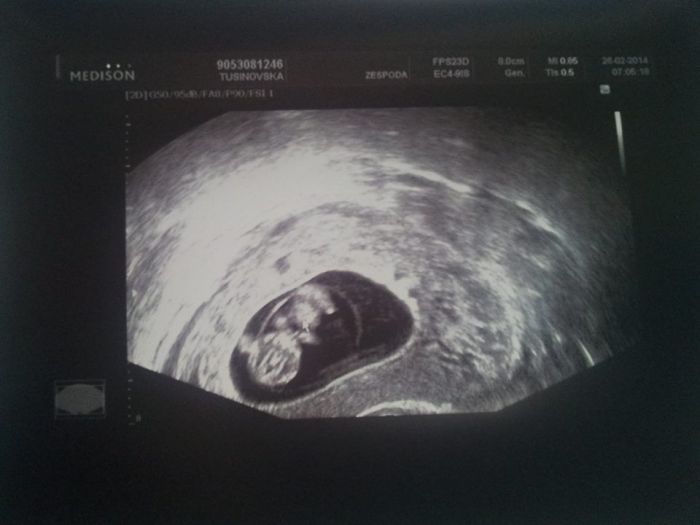

tak kontrolu mám úspěšně za sebou dle MS 9+3tt podle UTZ 9+6tt. Srdíčko tluče jako o závod a všechno je v pořádku... Další kontrola 11.3. kde už dostanu i průkazku. Spadl mi obrovský balvan ze strdce. V noci jsem ani nemohla spát, jak jsem byla nervózní. Jak se máte vy, holky???